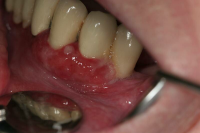

Akut inflammatorisk destruktiv sjukdom i gingiva och parodontium.

Karakteriseras av approximala nekrotiska och fibrintäckta sår (nedsmälta papiller) som är smärtsamma vid beröring och mycket lättblödande.

Patienten kan ha påverkat allmän tillstånd och ofta foeter ex ore.

I anamnesen förekommer ofta kombination av nedsatt immunförsvar, rökning, stress och dålig munhygien. HIV/Aids kan finnas som bakgrundsfaktor.